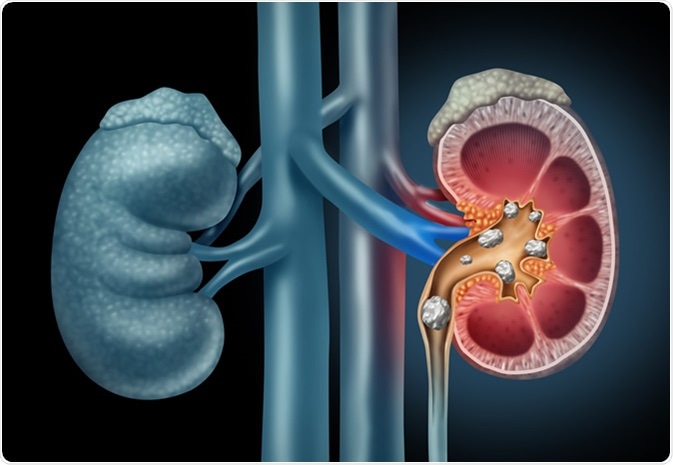

Kidney stones

Kidney stones form when there is a decrease in urine volume or an excess of stone-forming components in the urine. A kidney stone may not cause any symptoms unless it moves around within the kidney and passes down in the ureter. Severe pain may then occur in the side and back, below the ribs, and can radiate to the lower abdomen and groin area.

Human Kidney stones medical illustration. Image Credit: Lightspring / Shutterstock